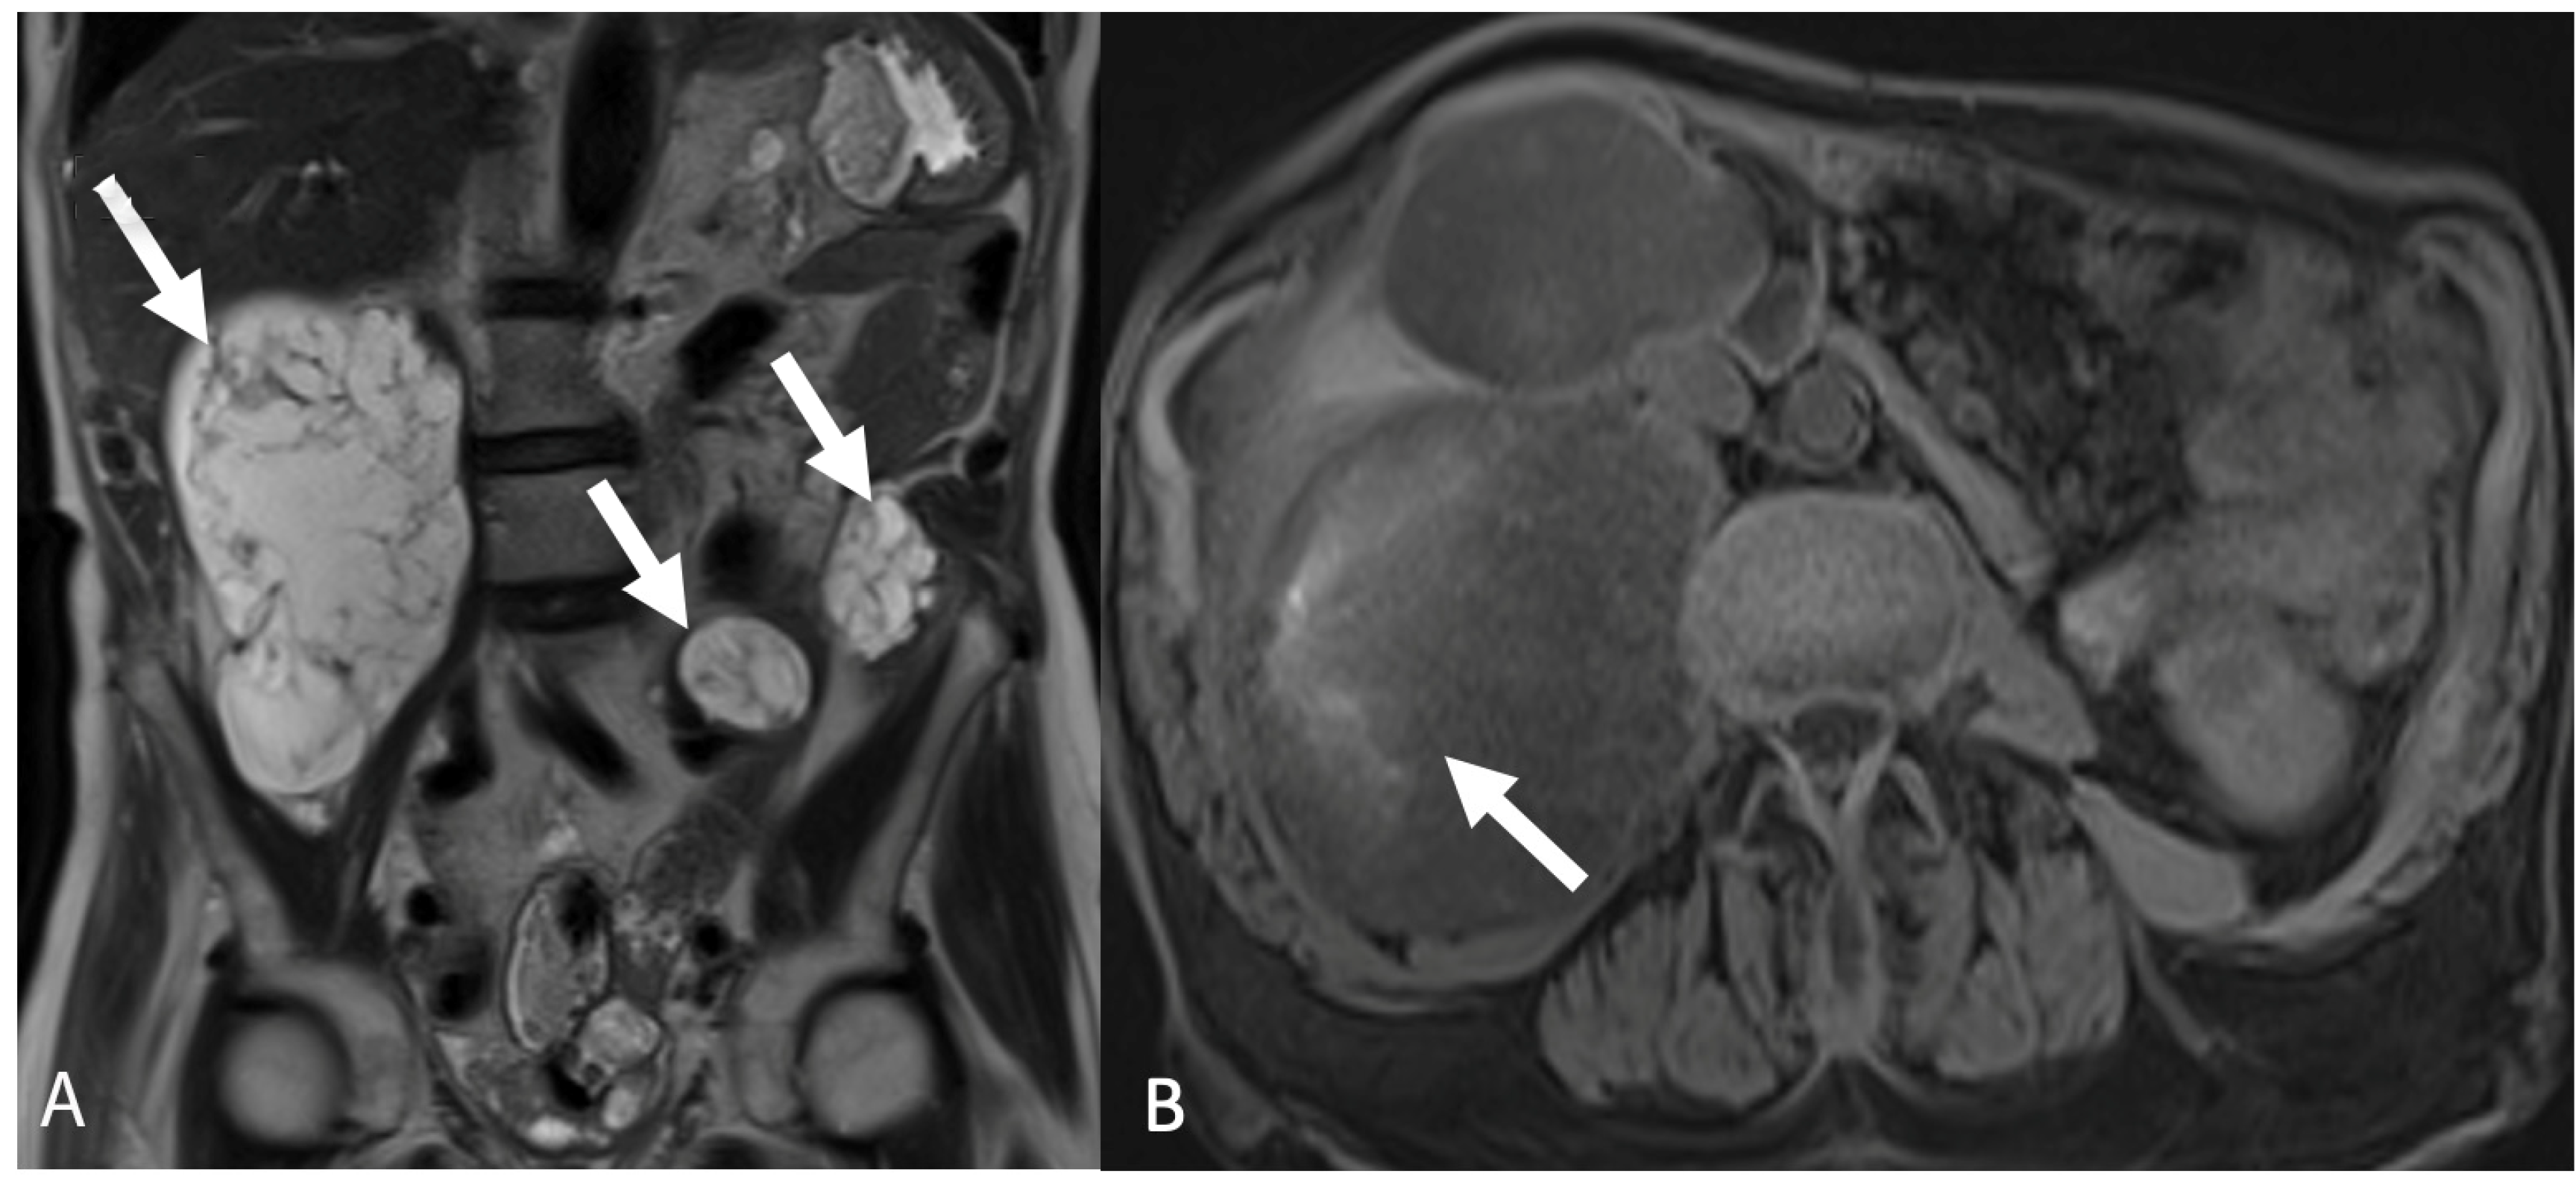

5.3. Peritoneal Disease

5.3.2. Peritoneal Carcinomatosis